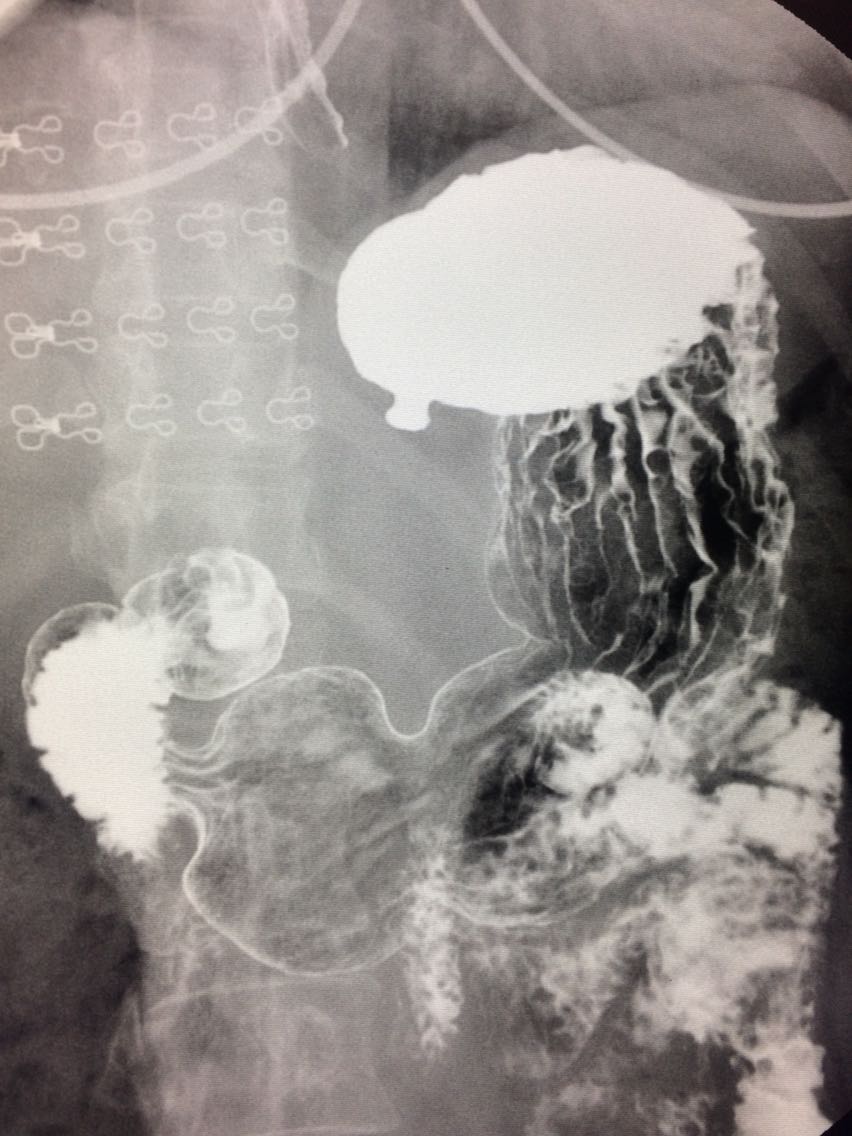

胃底憩室一例

胃憩室与胃壁内憩室

女.47岁 体检来诊。 平素体健,无明显症状。 做上消化道造影如图。

诊断,胃底憩室。 治疗,患者无明显症状,未予治疗。